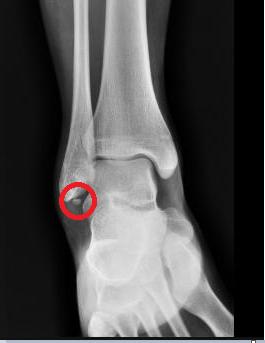

아래 X-ray는 비골 아래에 위치한 뼈조각이며 Os subfibulare라고 부르는데 증상을 유발하지 않는다면 전혀 제거할 필요가 없는 부위입니다. X-ray를 찍다가 우연히 발견되는 경우가 많습니다.